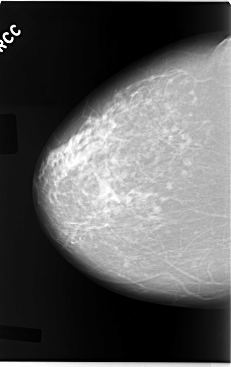

ics_version 1.0 filename C-0044-1 DATE_OF_STUDY 17 2 1993 PATIENT_AGE 64 FILM FILM_TYPE REGULAR DENSITY 2 DATE_DIGITIZED 5 11 1997 DIGITIZER LUMISYS LASER SEQUENCE LEFT_CC LINES 5872 PIXELS_PER_LINE 3624 BITS_PER_PIXEL 12 RESOLUTION 50 OVERLAY LEFT_MLO LINES 5816 PIXELS_PER_LINE 3648 BITS_PER_PIXEL 12 RESOLUTION 50 OVERLAY RIGHT_CC LINES 5864 PIXELS_PER_LINE 3688 BITS_PER_PIXEL 12 RESOLUTION 50 NON_OVERLAY RIGHT_MLO LINES 5848 PIXELS_PER_LINE 3744 BITS_PER_PIXEL 12 RESOLUTION 50 NON_OVERLAY |